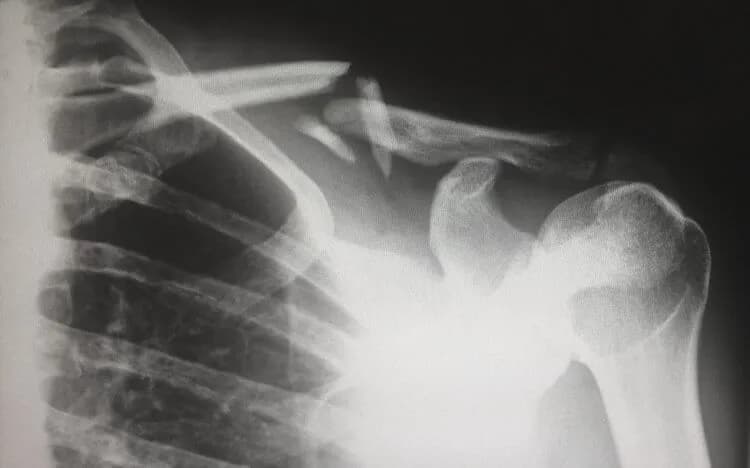

Tag jak długo trwa rehabilitacja po złamaniu obojczyka